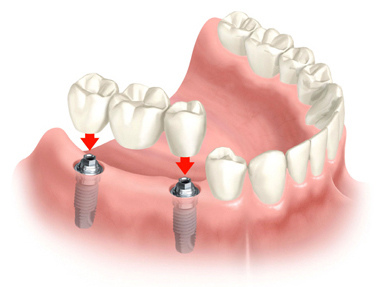

Implant

Implant là gì

Implant là một trụ Titanium nhỏ dài 10-15mm được cấy vào trong xương hàm để thay thế chân răng bị mất. Một khi trụ Titanium được tích hợp vào xương và lành hẳn thì lúc này nó trở thành một trụ rất chắc chắn và bền vững để có thể tiến hành làm các bước khác trên chân răng như mão răng, cầu răng hoặc làm các hàm giả bán hàm, toàn hàm, hàm cố định,...

Implant là giải pháp tối ưu nhất cho các trường hợp mất răng, những lợi ích mang lại từ việc cắm ghép Implant:

- Cảm nhận như một răng thật

- Giúp ngăn ngừa và giảm thiểu tình trạng tiêu xương

- Bảo vệ răng xung quanh chắc khỏe

- Tính thẩm mỹ cao

Quy trình cắm ghép Implant:

- Khám và tư vấn: Kiểm tra tổng quát tình trạng răng miệng, tiến hành chụp CT Scan. Phân tích, đánh giá cấu trúc xương cũng như độ dày của xương, lên kế hoạch chi tiết điều trị cho bệnh nhân

- Cắm implant: Nha sĩ chuyên cắm implant sẽ được chỉ định để thực hiện ca phẩu thuật, cần phải sử dụng thuốc tê trong suốt quá trình cắm, bệnh nhân nên chuẩn bị sức khỏe thật tốt, ăn uống đầy đủ và đặt biệt kiểm soát tốt chỉ số đường huyết.

- Giai đoạn chờ lành thương: thông thường cần phải chờ vài tuần đến vài tháng để trụ implant tích hợp với xương hàm.

- Hàm răng tạm: Nha sĩ sẽ làm răng tạm, cầu răng tạm tại vị trí mất răng trong lúc chờ vết thương lành để giữ được tính thẩm mỹ.

- Gắn Abutment: Sau khi vết thương lành hẳn thường từ 1 đến 6 tháng tùy cơ địa từng người, Nha sĩ sẽ gắn Abutment vào trụ Implant, sau đó Nha Sĩ sẽ lấy dấu gởi về Labo để hoan tất làm mão răng, cầu răng hay hàm răng.

- Gắn răng hoàn tất: Khi răng sứ đã sẵn sàng, Nha sĩ sẽ tháo bỏ răng tạm, cầu tạm và gắn răng sứ vào và hoàn tất quy trình cắm ghép.

- Chăm sóc: Cũng giống như răng thật, implant cũng cần phải được vệ sinh và tái khám định kỳ việc chăm sóc kỹ sẽ giữ răng được bền lâu hơn.

Tiến trình cắm implant có thể kèm theo trường hợp ghép xương, tùy vào cơ địa từng bệnh nhân mà Nha Sĩ sẽ đưa ra kế hoạch chi tiết trước khi tiến hành cắm ghép.